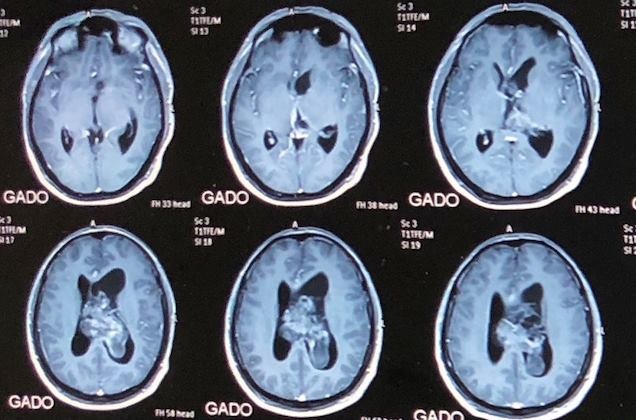

| Hình ảnh khối u trong não của nam bệnh nhân. Ảnh: BVCC. |

Bác sĩ Nguyễn Thanh Xuân, Phó trưởng khoa Phẫu thuật Thần kinh 1, người trực tiếp điều trị cho anh Lộc cho biết bệnh nhân vào bệnh viện khám phát hiện khối u lớn, kích thước (4,8x6,9 cm) gây chèn ép, tràn dịch trong não thất. Các bác sĩ đã hội chẩn và đi đến quyết định mổ não để cứu sống bệnh nhân vì nếu không được cấp cứu kịp thời, bệnh nhân có thể hôn mê và tử vong bất cứ lúc nào.